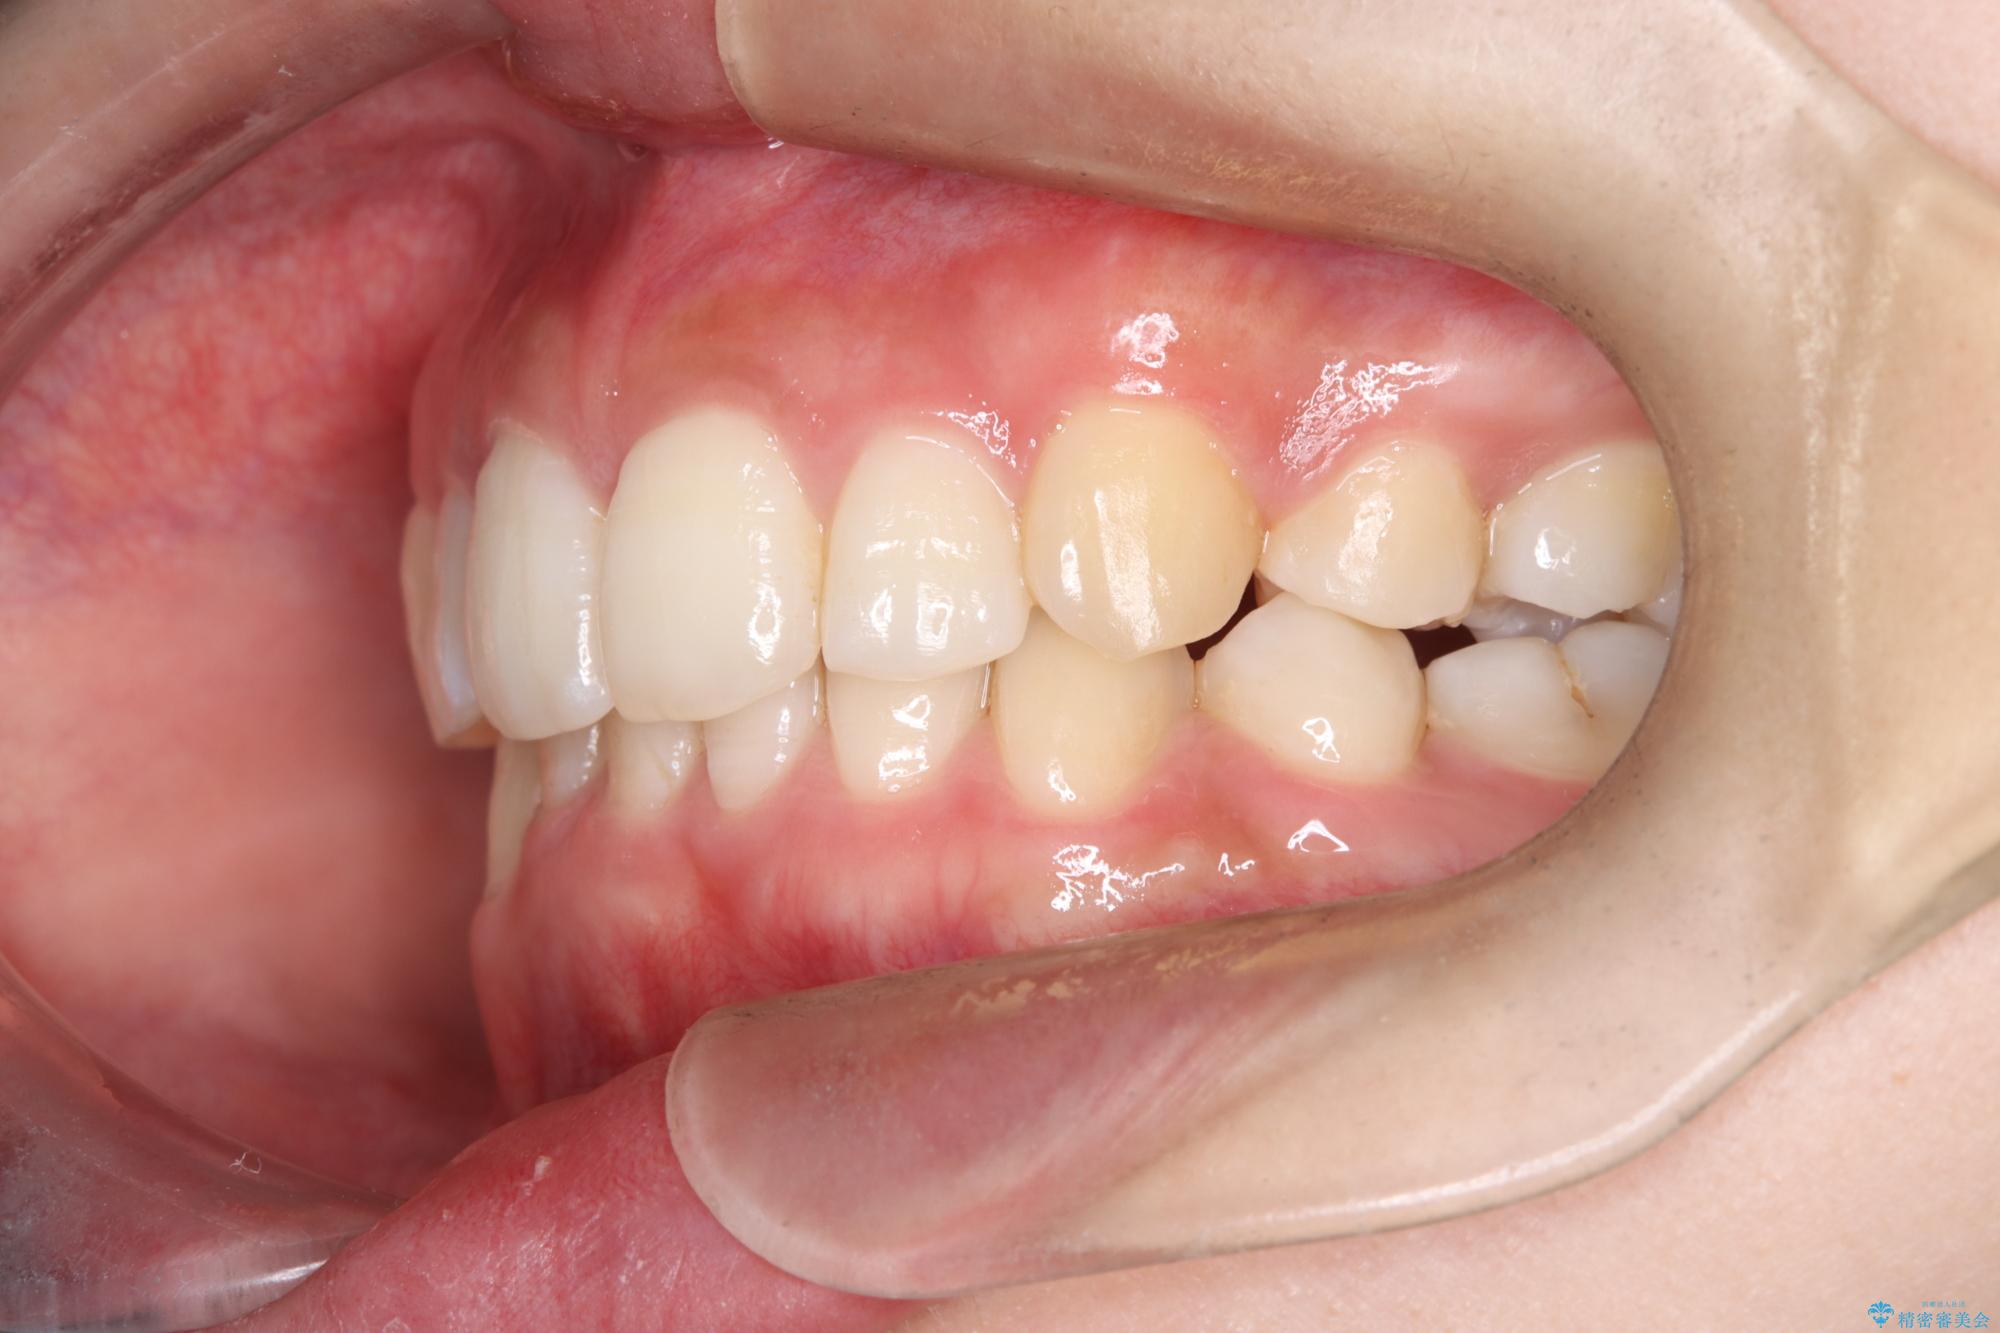

- 前歯から奥歯にかけて歯の重なりが激しい歯のがたつき(重度叢生)を主訴にご来院されました。精密検査の結果、歯が並ぶスペースが大幅に不足しており、歯並びを整え、口元を美しく引っ込めるためには、スペースの確保が必要と診断しました。そこで、上下左右の第一小臼歯(4番目の歯)を計4本抜歯し、そのスペースを利用して歯並び全体を整える抜歯矯正の治療計画を立案。装置には、透明で目立たないインビザラインを採用し、審美性と治療効果の両立を目指しました。

今回の治療では、重度の叢生を改善するため、まず計画通り上下左右4本の小臼歯を抜歯し、歯を並べるための十分なスペースを確保しました。装置には透明で取り外し可能なインビザラインを使用。抜歯によってできたスペースを最大限に活用し、マウスピースを定期的に交換しながら、デコボコを解消しつつ、前歯を効果的に後退させました。

治療の結果、長年の悩みであった重度の歯のがたつきが解消され、口元の突出感も改善。機能的にも安定し、審美的にも美しい、理想的な歯並びを獲得していただけました。